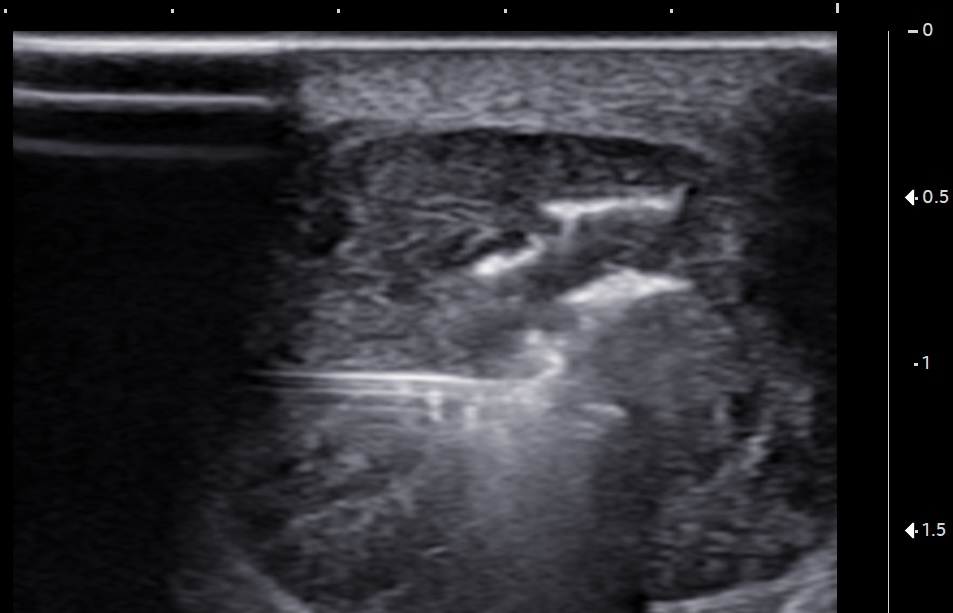

Short-axis ultrasound image of the midportion Achilles tendon showing the depth and width of the largest intrasubstance partial tear.